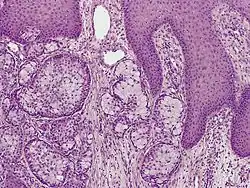

Eccrine carcinoma is a rare skin condition characterized by a plaque or nodule on the scalp, trunk, or extremities.[1]: 669  It originates from the eccrine sweat glands of the skin, accounting for less than 0.01% of diagnosed cutaneous malignancies.[2] Eccrine carcinoma tumors are locally aggressive, with a high rate of recurrence. Lack of reliable immunohistochemical markers and similarity to other common tumors has made identification of eccrine carcinoma difficult.[2]

A skin biopsy is the most common test used to diagnose eccrine carcinoma.[2] The biopsy will detect growth of new or abnormal tissue. Another test that can be performed is using immunohistochemistry, but it is inconsistent.[2] Markers used to detect eccrine carcinoma consist of carcinoembryonic antigen, progesterone receptors, estrogen receptors, epithelial membrane antigen, pancytokeratins, and cytokeratin 7.[5][6]